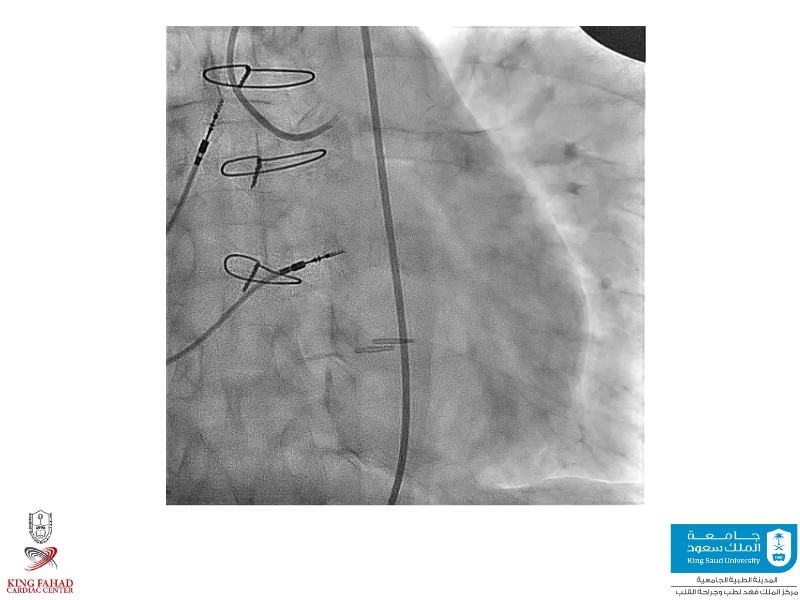

Second valve strategies with SAPIEN 3 Ultra RESILIA

This session helps you anticipate and address complex scenarios such as mitral valve-in-valve, TAV-in-SAV, and valve-in-valve-in-valve procedures. Learn from expert case discussions that explore procedural strategies, technical challenges, and best practices to optimize outcomes in redo structural heart interventions.